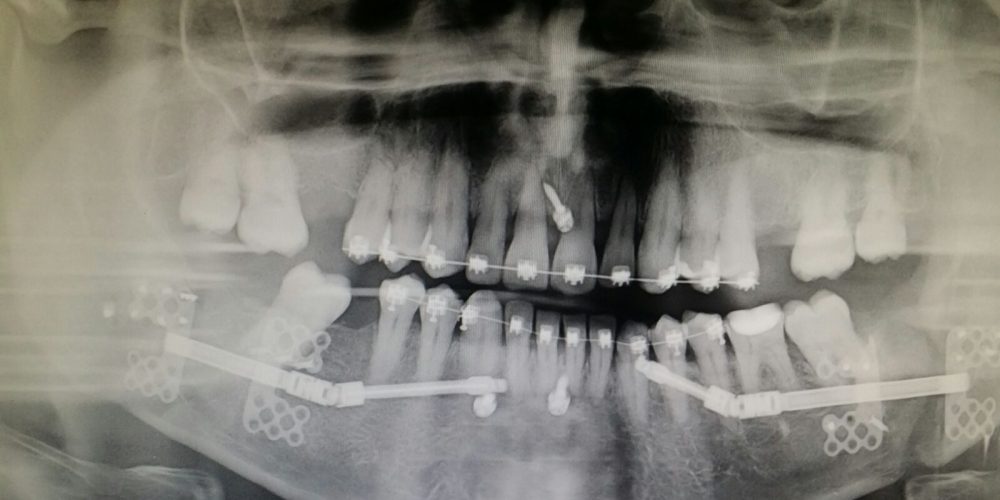

Categories Cirugía Maxilofacial Barcelona Posted on 04/06/2018 Paciente con apnea de sueño y mandíbula pequeña